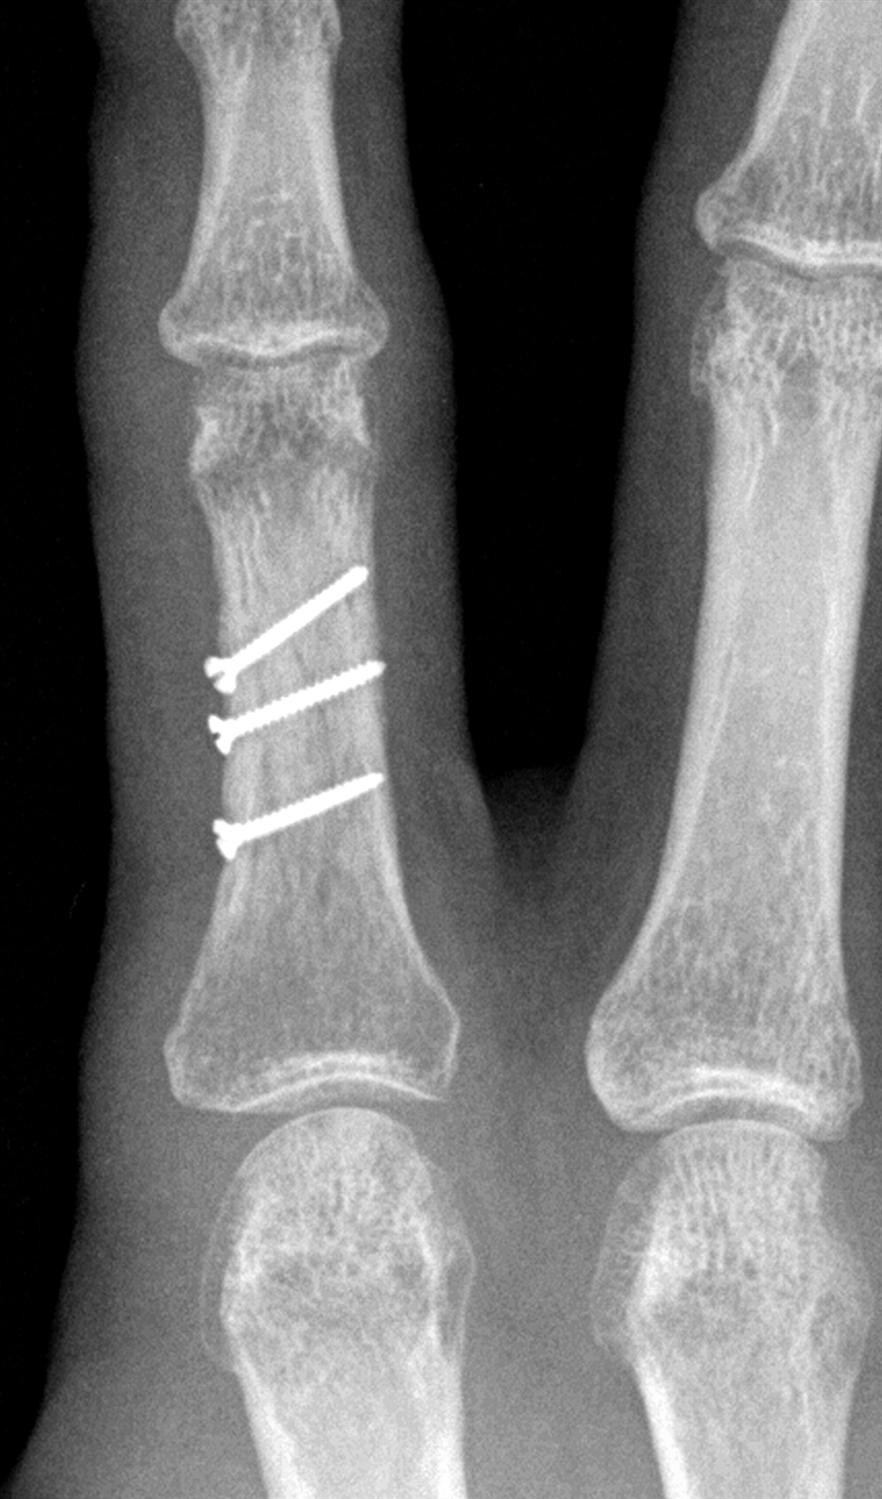

Phalanx Fractures Hand Orthobullets Crush Injury Finger Orthobullets Diagnosis is made clinically by physical. Nail bed injuries are the result of direct trauma to the fingertip and can be characterized into subungual hematoma, nail bed laceration, or nail bed avulsion. These fractures are commonly caused by trauma or crush injuries. 3 key points to keep in mind when approaching hand injuries: Complete — the entire fingertip is removed. Crush Injury Finger Orthobullets.

Phalanx Fractures Hand Orthobullets Crush Injury Finger Orthobullets These fractures are commonly caused by trauma or crush injuries. Partial — some structures remain attached; 3 key points to keep in mind when approaching hand injuries: Diagnosis is made clinically by physical. Extensor tendon injuries are traumatic injuries to the extensor tendons that can be caused by laceration, trauma, or overuse. Amputations of the fingertip may be: Diagnosis can. Crush Injury Finger Orthobullets.